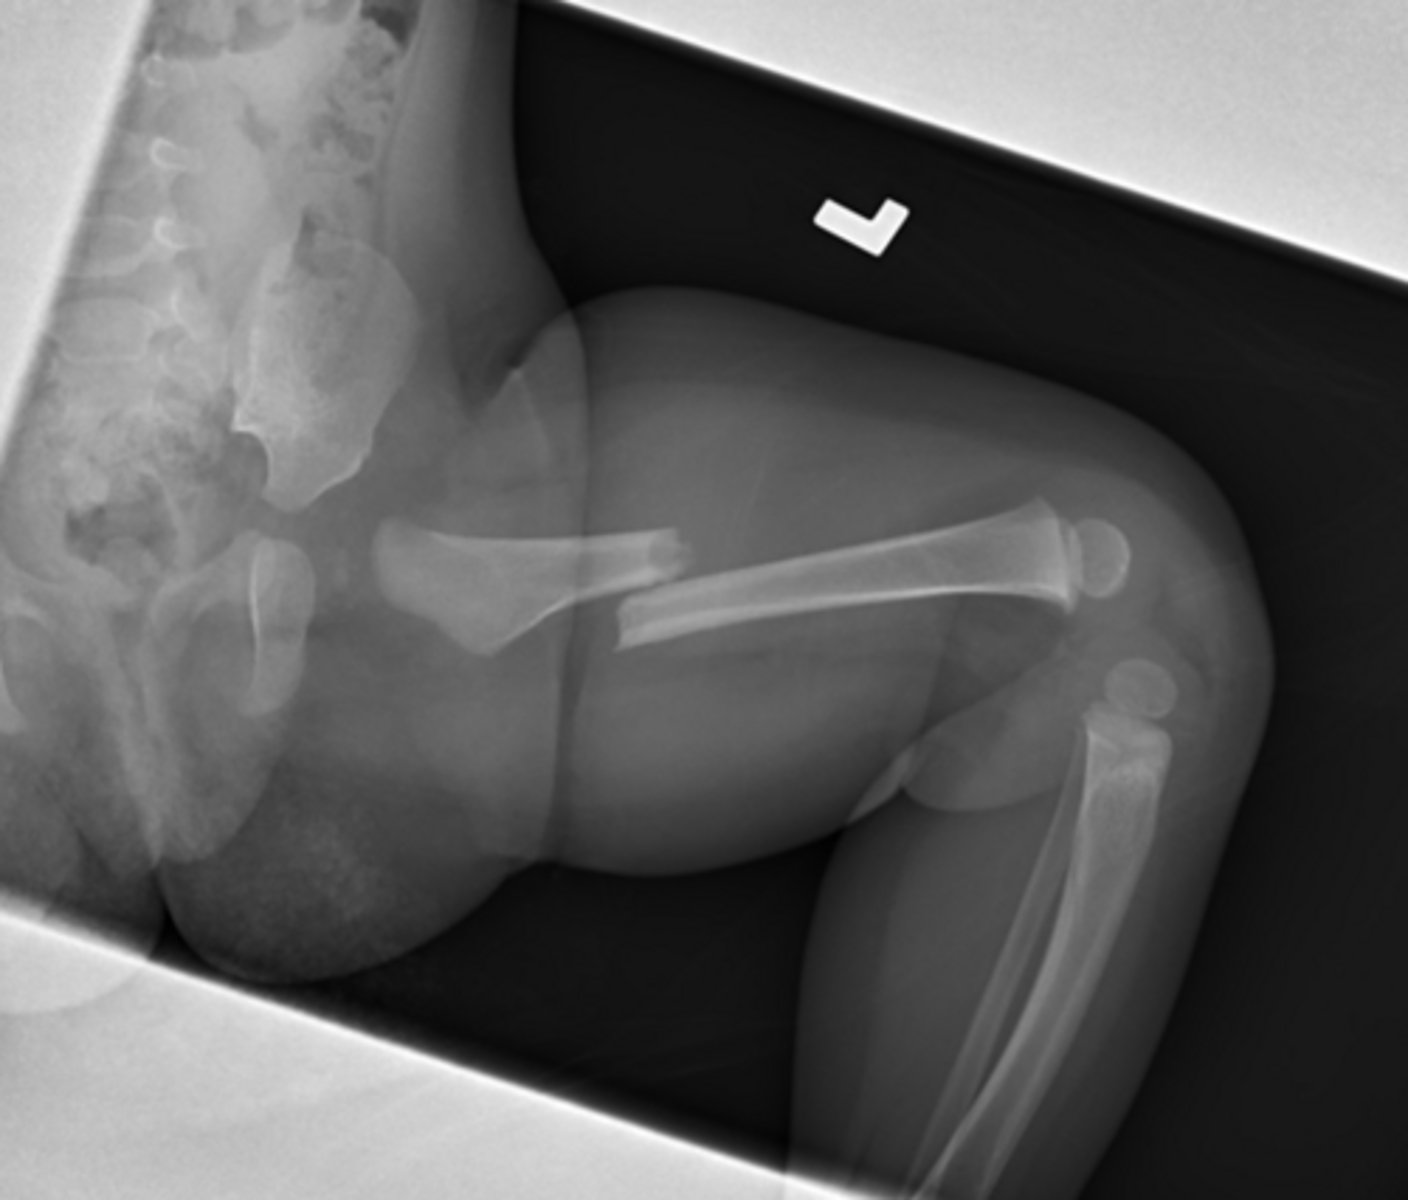

This is a 7 month old in tears

What do you want to do?

answer

Call CPS femur fx